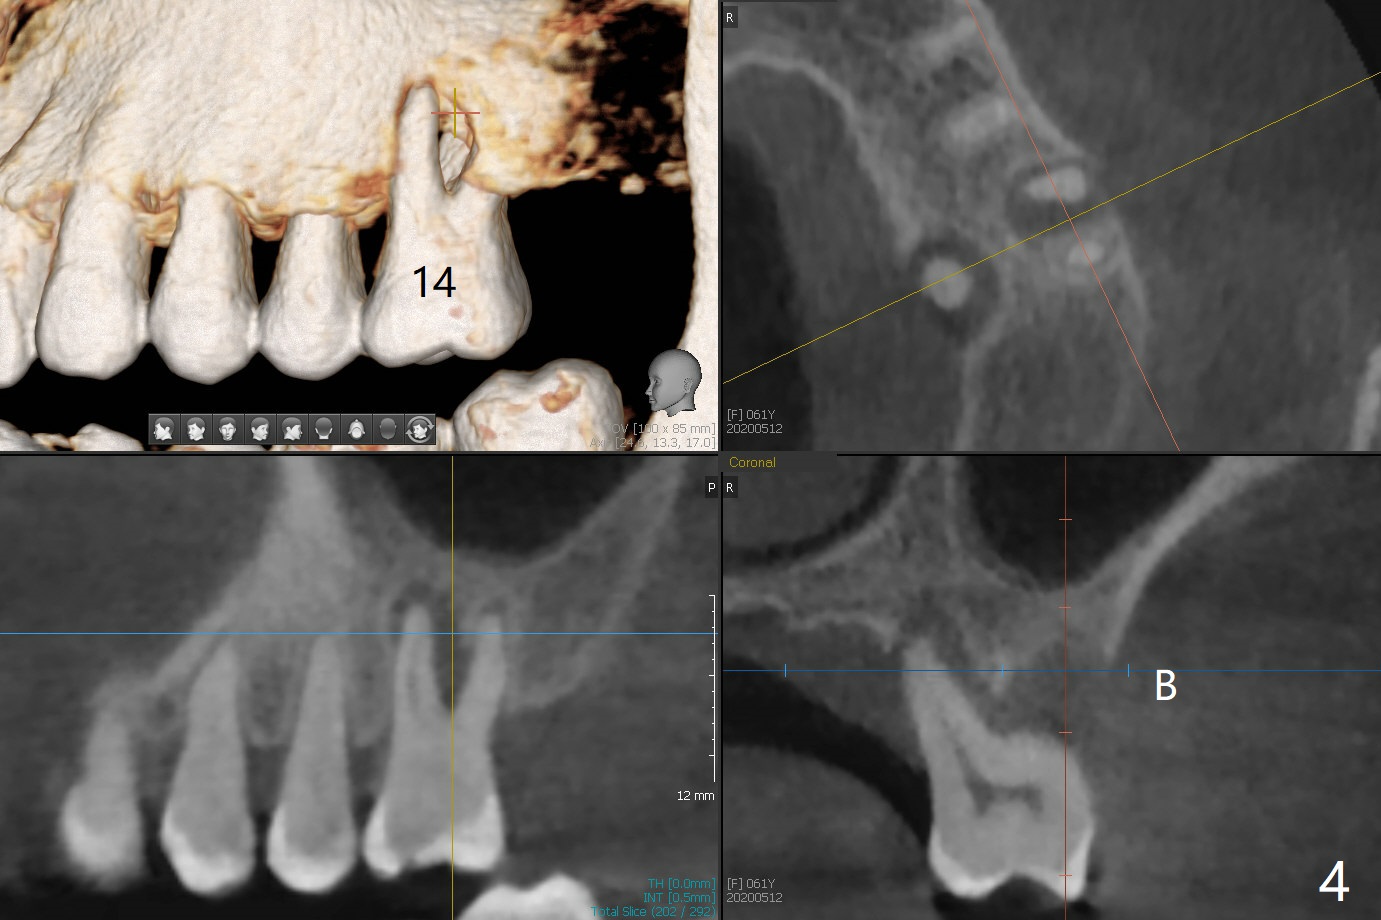

A 61-year-old woman with history of bruxism returns to clinic with chief complaint "I cannot chew bottom right. Top left has had pain and swelling before". Exam shows loose FPD at #31 (Fig.1) and necrosis of #14 (Fig.2). When the FPD is sectioned, the tooth #31 is found to have subgingival caries, filled with IRM (Fig.3). CT shows large PARL around MB and P roots of the tooth #14 (Fig.4), the fractured distal root of the tooth #19 with the low buccal plate (Fig.5) and a 5x10 mm implant being able to be placed at #30 (Fig.6). The crestal cortex (Fig.7 arrowheads) is thin in the edentulous area for several decades. The bone density is low (Fig.8, underprep). To place an implant over the pointed ridge, it should be trimmed prior to osteotomy (Fig.9). The bone loss associated with the fractured distal root is severe at #19 (Fig.10). After removal of the mesial root (Fig.11: 1), perform distal socket shield (2).